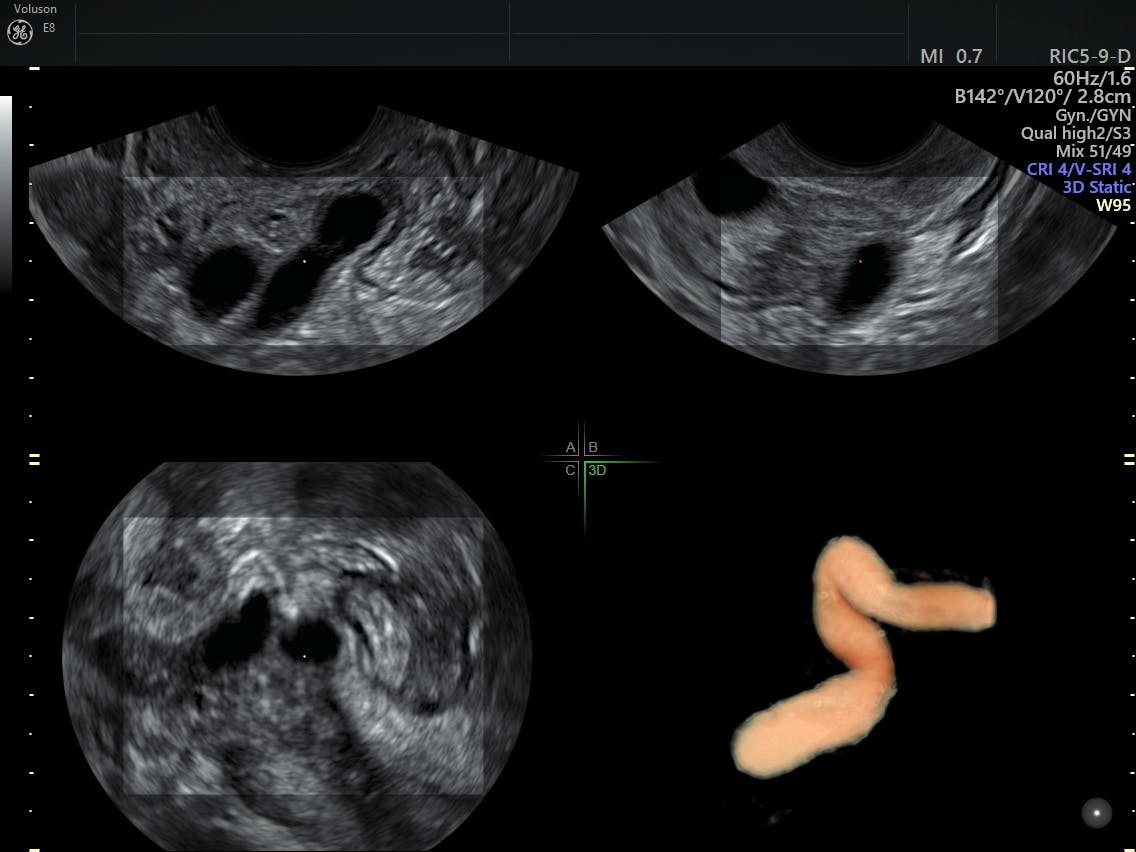

Biopsy which involves taking small tissue samples from the uterus. Pelvic sonography is performed commonly in patients who have a clinical diagnosis of pelvic inflammatory disease. Historically PID has been a clinical diagnosis supplemented with the findings from ultrasonography US or magnetic resonance MR imaging. A right adnexal dead end tubular fluid filled structure with typical mucosal infoldings toward the lumen thick wall and a debris-fluid level ultrasound image characteristic of a dilated fallopian tube in this case. Biopsy which involves taking small tissue samples from the uterus. A connected ultrasound system is another very helpful feature for the PID patient. Ultrasound findings of Pelvic Inflammatory Disease PID. Though PID is clinically diagnosed ultrasound imaging is the first-line radiologic evaluation method of choice for PID and may be used to appreciate the following. 20 21-year-old woman with pelvic inflammatory disease.